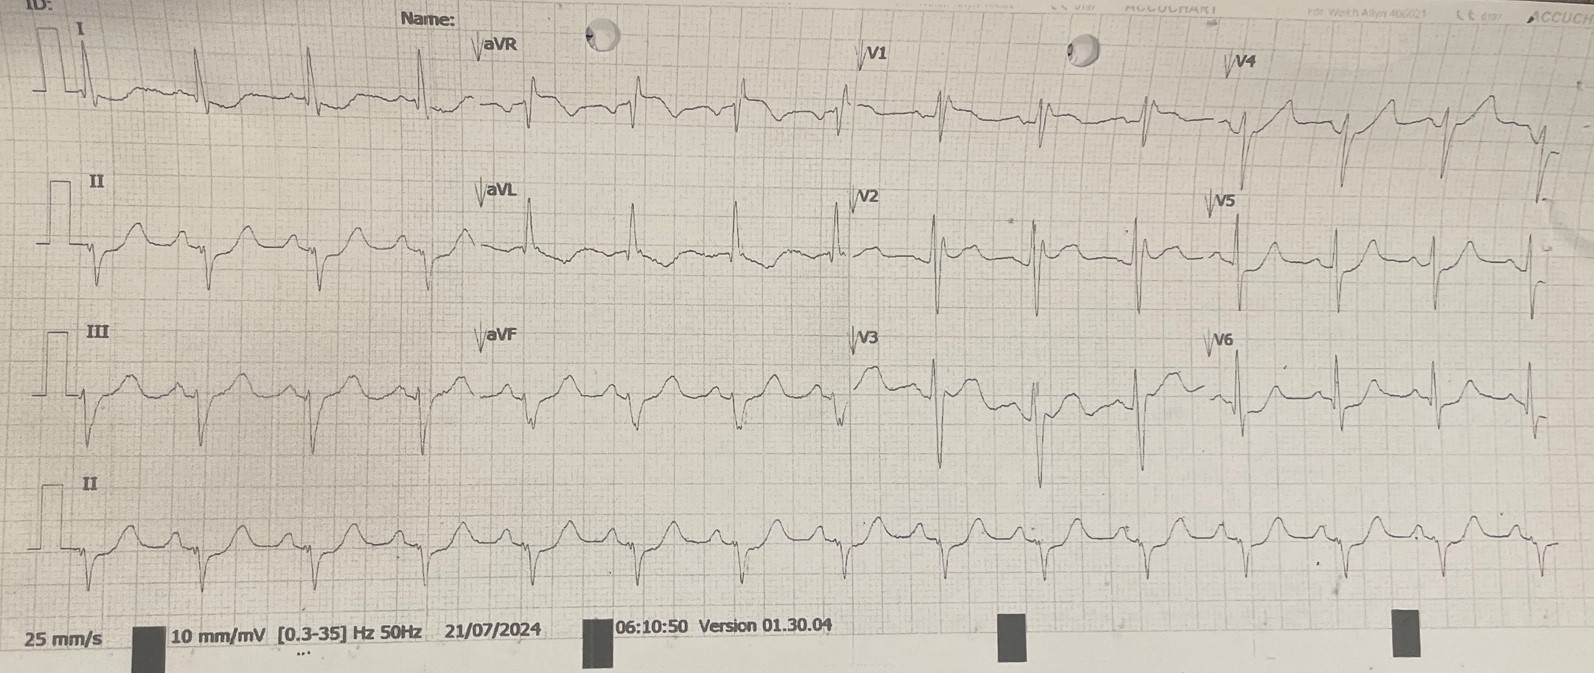

A case of a 44-year-old gentleman with epilepsy and coronary artery disease, who had angioplasty done to left circumflex artery with a DES in 2016. He complained of new onset of exertional angina for months and presented to hospital due to worsening symptoms. On presentation, he complained of ongoing chest pain, clinically not in failure with BP 100/62 mmHg, HR 74 bpm and SpO2 99% under room air. Lungs were clear, heart sound was normal with no murmur. ECG showed dynamic changes during chest pain.

Baseline ECG showed sinus rhythm with right bundle branch block. There were ST depression over lead I, aVL, V5 and V6 during chest pain. Laboratory examination showed creatine kinase level of 161 U/L (<200 U/L). Echocardiogram showed good LV systolic function, LVEF 65-70% with no RWMA, normal chamber size. He was treated for unstable angina and underwent in-hospital coronary angiography (CAG) and percutaneous coronary intervention (PCI) in view of recurrent angina.